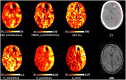

Metabolic derangements following traumatic brain injury are poorly characterized. In this single-centre observational cohort study we combined 18F-FDG and multi-tracer oxygen-15 PET to comprehensively characterize the extent and spatial pattern of metabolic derangements. Twenty-six patients requiring sedation and ventilation with intracranial pressure monitoring following head injury within a Neurosciences Critical Care Unit, and 47 healthy volunteers were recruited. Eighteen volunteers were excluded for age over 60 years (n = 11), movement-related artefact (n = 3) or physiological instability during imaging (n = 4). We measured cerebral blood flow, blood volume, oxygen extraction fraction, and 18F-FDG transport into the brain (K1) and its phosphorylation (k3). We calculated oxygen metabolism, 18F-FDG influx rate constant (Ki), glucose metabolism and the oxygen/glucose metabolic ratio. Lesion core, penumbra and peri-penumbra, and normal-appearing brain, ischaemic brain volume and k3 hotspot regions were compared with plasma and microdialysis glucose in patients. Twenty-six head injury patients, median age 40 years (22 male, four female) underwent 34 combined 18F-FDG and oxygen-15 PET at early, intermediate, and late time points (within 24 h, Days 2-5, and Days 6-12 post-injury; n = 12, 8, and 14, respectively), and were compared with 20 volunteers, median age 43 years (15 male, five female) who underwent oxygen-15, and nine volunteers, median age 56 years (three male, six female) who underwent 18F-FDG PET. Higher plasma glucose was associated with higher microdialysate glucose. Blood flow and K1 were decreased in the vicinity of lesions, and closely related when blood flow was <25 ml/100 ml/min. Within normal-appearing brain, K1 was maintained despite lower blood flow than volunteers. Glucose utilization was globally reduced in comparison with volunteers (P < 0.001). k3 was variable; highest within lesions with some patients showing increases with blood flow <25 ml/100 ml/min, but falling steeply with blood flow lower than 12 ml/100 ml/min. k3 hotspots were found distant from lesions, with k3 increases associated with lower plasma glucose (Rho -0.33, P < 0.001) and microdialysis glucose (Rho -0.73, P = 0.02). k3 hotspots showed similar K1 and glucose metabolism to volunteers despite lower blood flow and oxygen metabolism (P < 0.001, both comparisons); oxygen extraction fraction increases consistent with ischaemia were uncommon. We show that glucose delivery was dependent on plasma glucose and cerebral blood flow. Overall glucose utilization was low, but regional increases were associated with reductions in glucose availability, blood flow and oxygen metabolism in the absence of ischaemia. Clinical management should optimize blood flow and glucose delivery and could explore the use of alternative energy substrates.